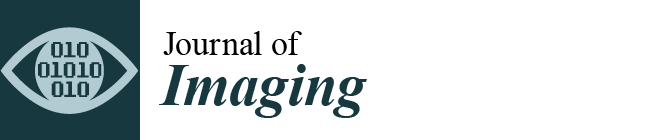

3.1. WD Affects Body Weight and Nutritional Phenotype of C57Bl/6J Mice

3.2. WD Influences Feeding Behavior in C57Bl/6J Substrain